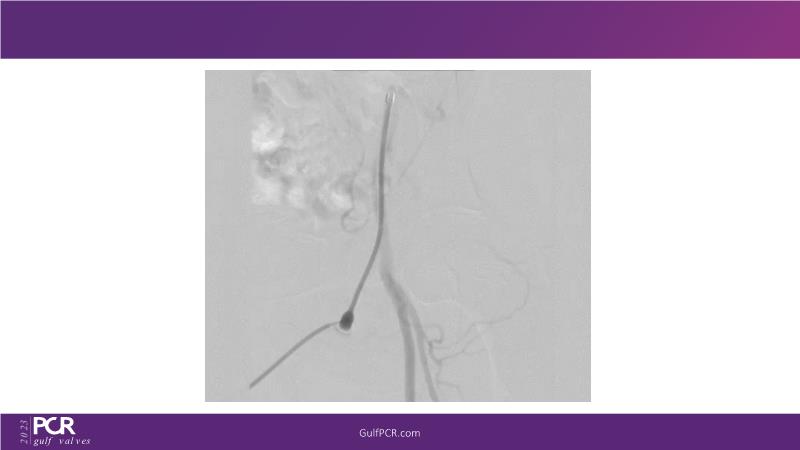

The primary focus of this GulfPCR-GIM 2023 session revolves around pre-procedural planning considerations, valve selection, and managing complex anatomies using both traditional self-expanding valves and the Evolut FX system. Additionally, the session aims to explore the work-up protocol for patients grappling with severe AS and advanced CKD, elucidate the algorithm for selecting the appropriate TAVR platform, discuss strategies to reduce contrast utilization, and highlight the distinctive advantages offered by the Evolut FX system.

• To discuss challenges in TAVI procedural planning

• To discuss valve choice in challenging anatomies

• To learn more about optimization of valve deployment